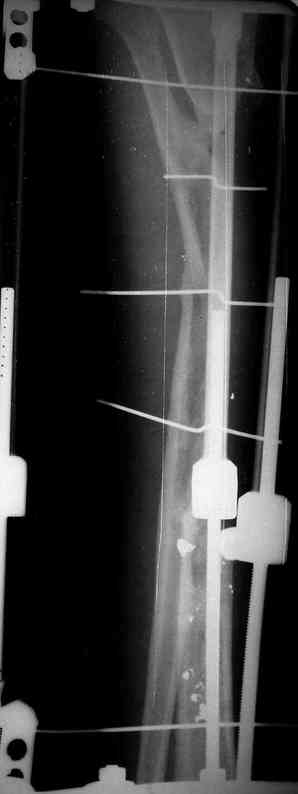

5. Ну и чтобы не быть голословным. Молодой человек подорвался на фугасе (Чечня, 2005 год). Свежие рентгенограммы:

Соответственно ожоги и дефект мягких тканей, переломы костей стопы и пр. Наложили аппарат

Илизарова (как придется), хирургически обработали и героически заживляли мягкие ткани с многочисленными кожными пластиками. В итоге через полгода я принял его вот таким:

Реализовал описанную выше методику, и в итоге вот что получилось. Высылаю лишь прямые проекции,

Очень пригодились карбоновые кольца (Джолдас -огромное спасибо, я твой должник!!!), поскольку остеопороз дистального отломка был просто невероятный. На цифровом рентгене с трудом угадывались контуры.

Рентген в процессе перемещения - внизу карбоновые кольца, тракция фрагмента спицами с упором.

внешний вид в аппарате - не завершающем этапе, сначала стопа тоже была фиксирована в аппарате.

Сейчас аппарат сняли, но случай ещё не завершенный.

Признаюсь честно, не совсем уверен в прочности консолидации на стыке косточек. Кроме того, укорочение в районе 6 см. Сейчас реабилитация - ходит опираясь на ногу с одним костылем.

Продолжение, видимо, будет... Возможно, будем удлинять.